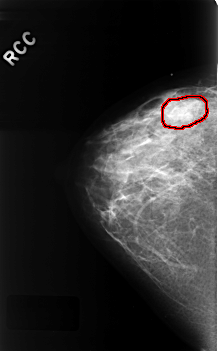

C_0330_1.RIGHT_CC

RIGHT_CC LINES 4560 PIXELS_PER_LINE 2824 BITS_PER_PIXEL 12 RESOLUTION 50 OVERLAY

FILE: C_0330_1.RIGHT_CC.OVERLAY

TOTAL_ABNORMALITIES 1

ABNORMALITY 1

LESION_TYPE MASS SHAPE LOBULATED MARGINS OBSCURED

ASSESSMENT 3

SUBTLETY 2

PATHOLOGY BENIGN

TOTAL_OUTLINES 1

BOUNDARY